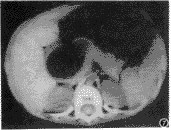

囊性淋巴管瘤:为均匀水样密度的多房或单房薄壁囊性肿块,大小4cm×3cm×8cm~8cm×7cm×10cm(图2),增强后,囊壁轻度均匀强化,大部分形态规整,界清,周围组织轻度受压移位,但其中有1例肠系膜上巨大囊性无分房、均匀水样密度、无壁的囊性淋巴管瘤术前CT误诊为腹水。

图2 囊性淋巴管瘤,为薄壁囊性包块,其内均匀水样密度